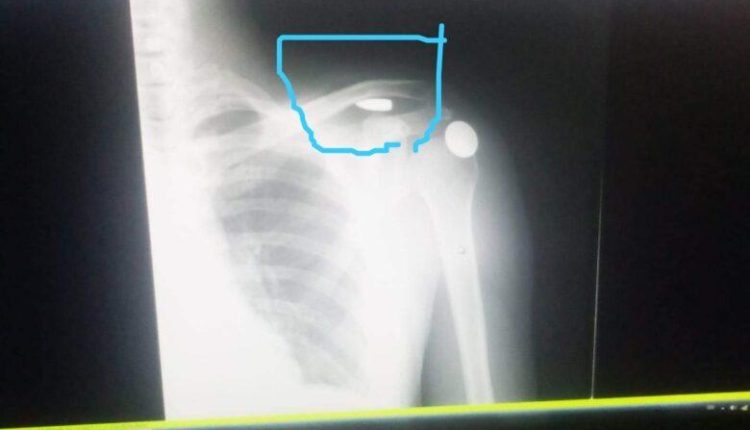

الرحلة بدأت عندما ذهب إلى مستشفى الشونة ليخبروه بأنه مصاب بعيار ناري، ولم يحاولوا استخراج الرصاصة من كتفه، حيث أخبره الطبيب أن الرصاصة ممكن أن تبقى في كتفك بشكل طبيعي، ليخرج من المستشفى دون أن يتم إزالة الرصاصة. وصرح مدير مستشفى الشونة الجنوبية عوض الخزاعلة بأن موقع الرصاصة حساس، وموجود بالقرب من الجهة العلوية للرئة، وتبعد بمسافة قصيرة جدا عن شريان رئيسي مغذي للكتف.

وأضاف : “تم إجراء عملية موضعية ببنج موضعي، من أجل إخراج الرصاصة، لكن الطبيب تفاجأ من وجودها بمكان حسّاس جدا”، مشيراً أنه لا ضير من ترك الرصاصة بمكانها، إلى حين تحويل المريض إلى مستشفى آخر، يوجد فيه جرّاح رئة وأوعية دموية وعظام”